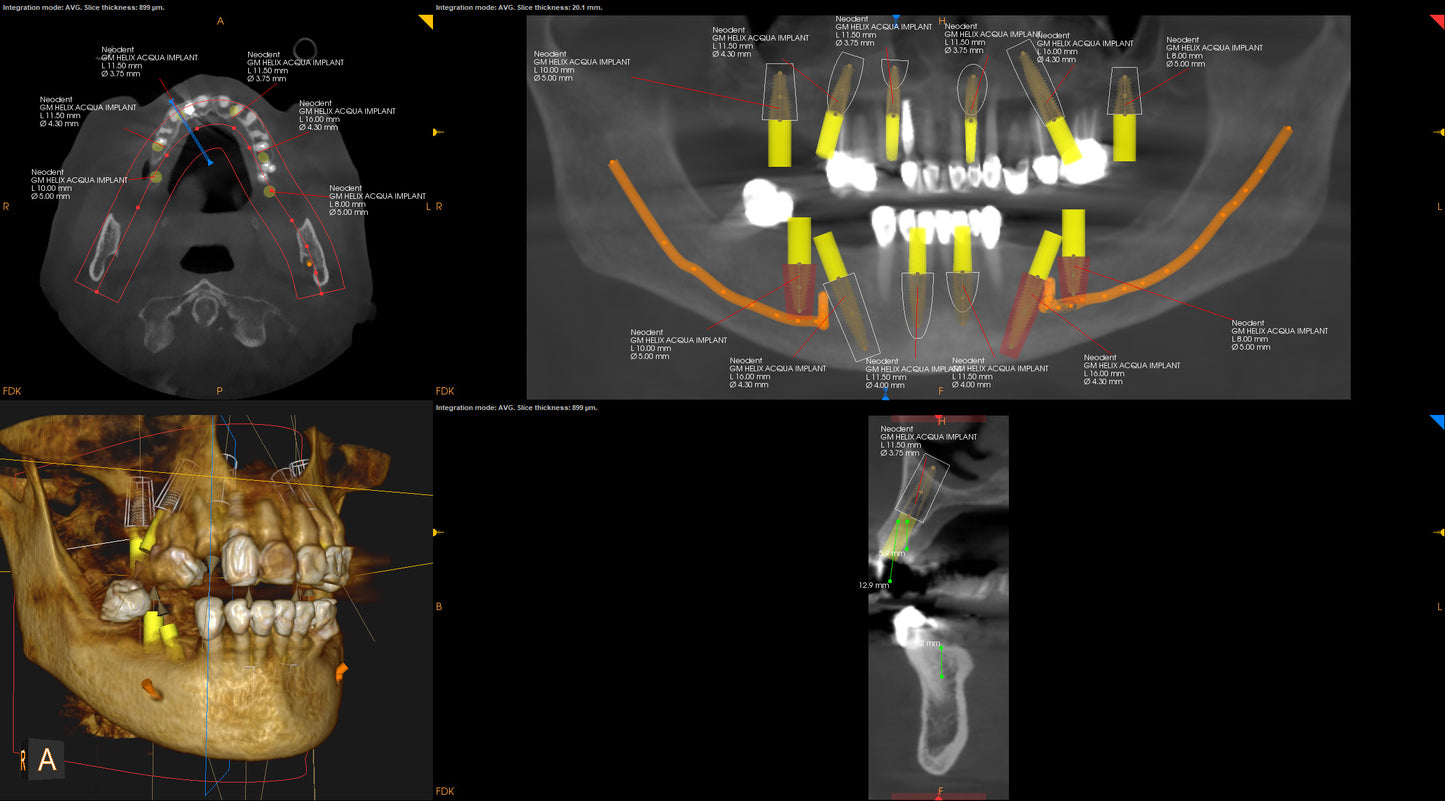

- Learn case selection, CBCT radiographic interpretation, case presentation, digital case planning for analog and digital workflows.

The Atlantic Implant Institute is proud to partner with Art of Arches for the Fundamentals of Full Arch Surgery and Prosthetics. This course is a beginner course that offers a combination of in-depth didactic lectures, hands-on workshops, open discussions, and live patient demonstrations. Doctors, lab technicians, and team members will experience first-hand how to implement full arch procedures into their practice. The topics and techniques covered throughout the course includes treatment planning, case selection criteria, 3D imaging interpretation, surgical tips, prosthetic treatment, implant placement, and full-arch/teeth-in-a-day conversion protocols.